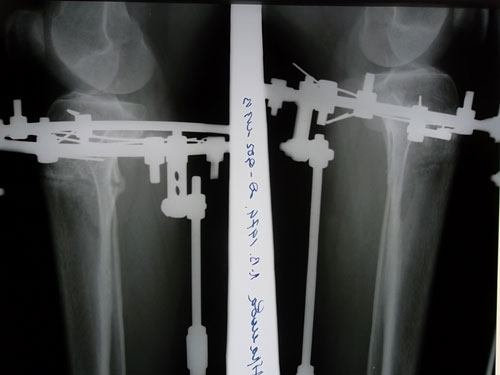

Дата операции 14.08.2012г.

Дата снятия аппаратов 15.11.2012г.

Срок лечения 90 дней.

В аппаратах в день снятия.

Привет всем! Огромное спасибо за поздравления! Отдельное спасибо Николаю Николаевичу и всему мед .персоналу!Приехала с утра в Павлодар на снятие,в 10 утра на снимок,(а сама заранее взяла билет на вечер домой),доктор посмотрел рентген и сказал-"Все отлично,можно снимать!" Укол обезболивающий не делала, так снимали ))))))Вообщем потерпеть можно было.Сняли аппараты очень быстро,сфоткали и всё!!!!!!!!!!!! Я свободна!!!!!!!А вечером уехала домой! Походка конечно еще не как у модели,но потихоньку расхаживаюсьПриехала домой ,набрала ванну и сбылась моя мечта!!!!!!!!! В ногах под коленями еще чувствуется стянутость,как будто мышцы напряжены.Ну а вообщем,я очень рада. Всем привет! Удачи!